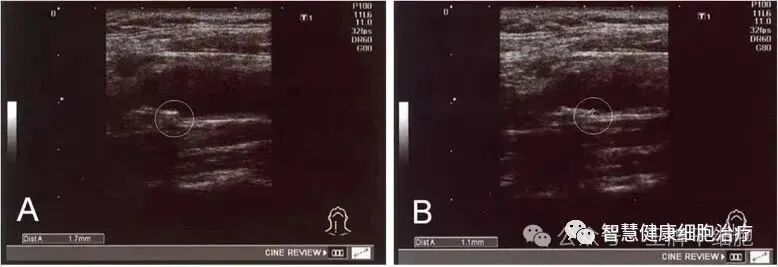

图片

△ 经过治疗,实验中一名患者 IMT 从 1.7 毫米降至 1.1 毫米

实验证实:干细胞可以改善血清中的高密度脂蛋白,低密度脂蛋白和残余样颗粒胆固醇水平,调节脂质代谢,能够安全有效地改善动脉粥样硬化。